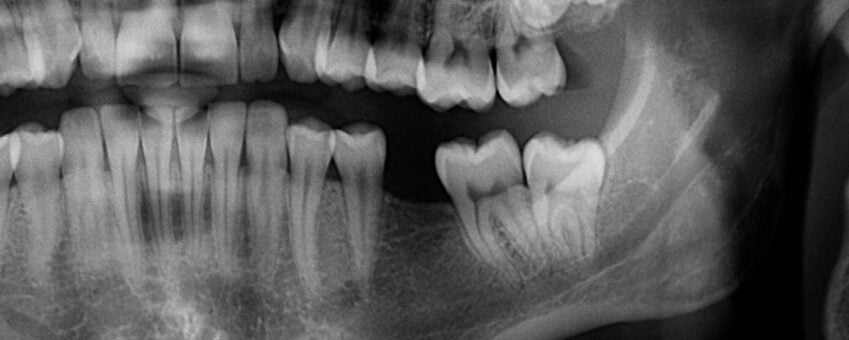

A tooth may require extraction for a variety of reasons. If the tooth is impacted in the gumline (particularly common with wisdom teeth), if there are serious crowding issues, or if the tooth is too damaged, rotted, or loose to be saved with root canal treatment, Dr. Cabanban may determine that extraction is the best option. After the recovery period is over, it will be time to begin taking the prosthodontic or orthodontic steps needed to fill in your smile.